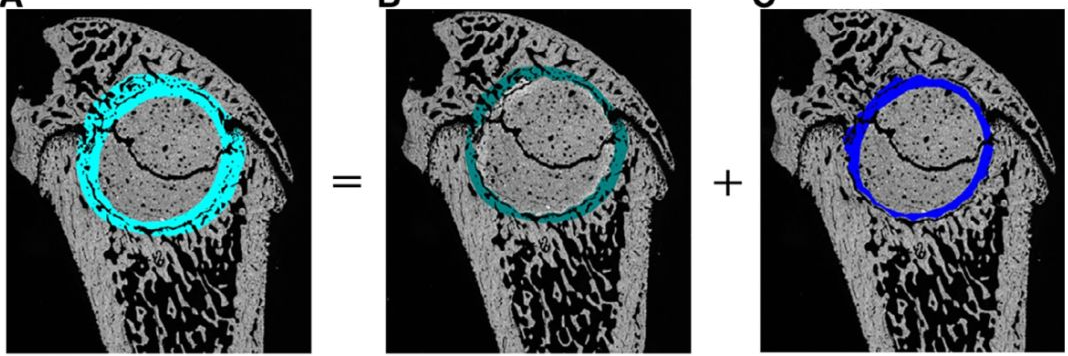

1、脚印面积 (cm2) 是在站立时相完整脚印的表面积(图2B)。

2、脚印平均接触强度(AU):完整脚印在一个步长周期中步态支撑期接触的平均强度(图2C)。

(A)对照组大鼠在CatWalk系统上的背景图;(B)术前的CatWalk脚印(脚印面积)左脚印红色,右脚印蓝色,后肢显示浅色,前肢深色;(C)一个正常大鼠的右后腿爪,显示出的手动脚印测量长度和脚印接触强度;(D)术前CatWalk步态图